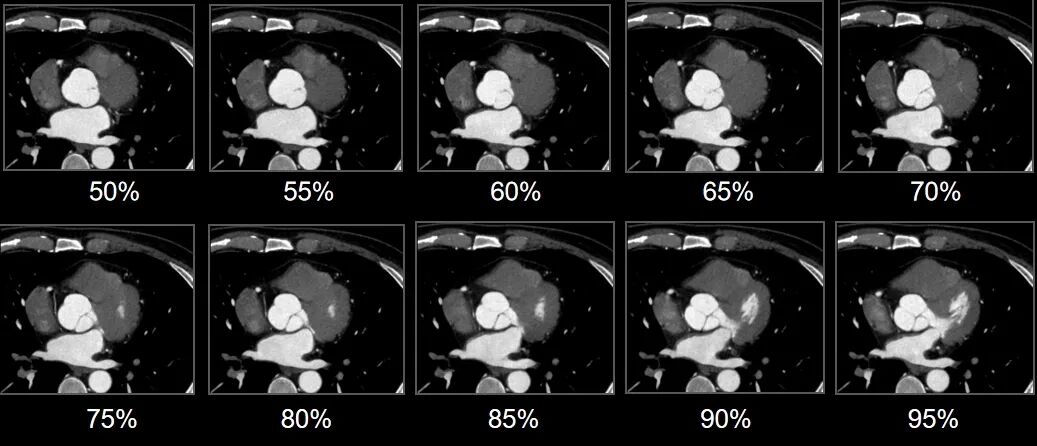

一直以来,冠脉CTA扫描对患者心律和扫描条件要求较高,传统单源宽体系统受限于时间分辨率,往往在心脏收缩末期或舒张中期获得可用于临床诊断的冠脉CTA图像。

令人欣喜的是,uCT SiriuX凭借8ms超高时间分辨率和全心覆盖,可以做到在单心动周期内的任意时相获取高质量的冠脉CTA图像

我们来看成像效果!

什么是联影ct真香预警?联影医疗双宽体双源CT大揭秘!TA竟然可以看到心脏的高清运动!_https://www.jmylbn.com_新闻资讯_第17张

什么是联影ct真香预警?联影医疗双宽体双源CT大揭秘!TA竟然可以看到心脏的高清运动!_https://www.jmylbn.com_新闻资讯_第18张

什么是联影ct真香预警?联影医疗双宽体双源CT大揭秘!TA竟然可以看到心脏的高清运动!_https://www.jmylbn.com_新闻资讯_第19张

单心动周期全心全时相高清成像图